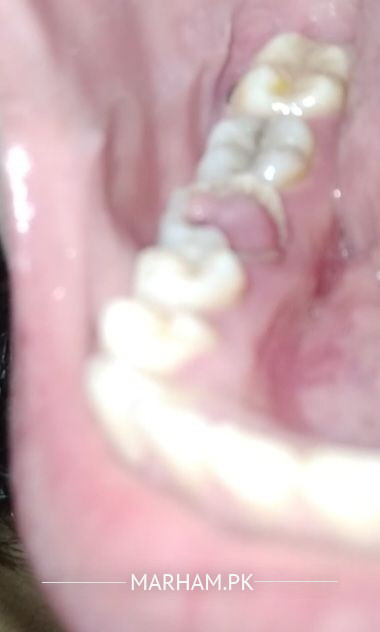

mere problem ye hai k me jb bhe raat ko sote hu subha uthe hu tu danto se khoon nikla howa huta haiii ajeeb si smeel hute hai jb bhe dant brush krte hu tu masoro se khoon nikl ata haii mere teeth ka yee masla mujhe kafi dino se haiii dant bhe brush krte hu leken her bar yhi masla pesh ata hai me ne ak pic bhe share ki hai phle mere danto me cavity the ab wo nhi hai leken os jgha pr space a gyaa or os jgha pr ghost oper hu gya haii ab jb bhe bursh krte hu ya raat sote hu tu bleeding hute hai plzzz kuch bta den es bare me

this lower first molar is damaged needs radiograph .periapical for this tooth and for all teeth better to do opg radiograph.

extraction

kind of pulp polyp

Ye dant crack hai or is ko nikalna hoga . Xray zaroori hai .

dant ko nikalna ho ga is mei reesha bhar raha hai aur yeh bharta rahe ga jab tak is dant ko nikal na diya gaya zuban ke side per zakham isey dant ke waja se hai jis mei se khoon ata hai.

is side per khana na chubaye